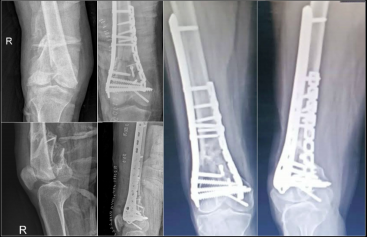

2.雙鋼板固定

目前,雙鋼板固定或釘板聯(lián)合固定形式已成為大多數(shù)老年股骨遠(yuǎn)端骨折的首選治療方法。

這種固定方式能滿足老年股骨遠(yuǎn)端骨折對(duì)穩(wěn)定性的更高要求,尤其適用于關(guān)節(jié)內(nèi)骨折和伴有干骺端粉碎的骨折類型。其額外增加的內(nèi)側(cè)鎖定鋼板提升了整體結(jié)構(gòu)的生物力學(xué)穩(wěn)定性,提供的抗扭轉(zhuǎn)穩(wěn)定性遠(yuǎn)高于單一外側(cè)鋼板。

股骨遠(yuǎn)端外側(cè)接骨板

型號(hào):DCA24

規(guī)格:5-13孔

長(zhǎng)度:156-316mm